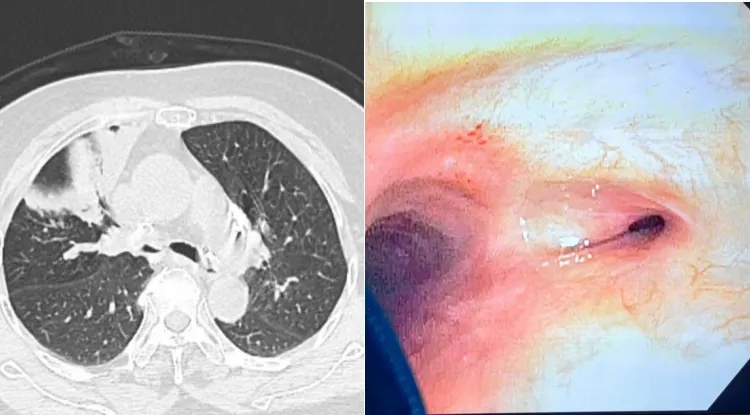

患者黄女士(化名),70岁,因“反复气促、咳嗽、发热加重1月”入院。既往有肺结核病史,影像学检查显示右主支气管重度狭窄(狭窄度>80%),右肺通气功能严重受损,反复肺部感染,日常活动受限。传统治疗方案创伤大、恢复慢,治疗效果差;入院完善相关检查,经科室讨论后,建议行支气管镜下球囊扩张术,解决患者的根本问题。

1.精准定位:在全麻下,张冀松博士、安宇主任领衔团队将支气管镜经气管插管送入气道,高清镜头实时锁定狭窄部位(右主支气管);

3.即时显效:术后管腔直径扩大至正常水平的80%,术后患者感觉“呼吸畅通”,血氧饱和度升至96%。

术后效果:患者胸闷、气促症状显著缓解,复查显示肺不张区域复张,生活质量大幅提升。